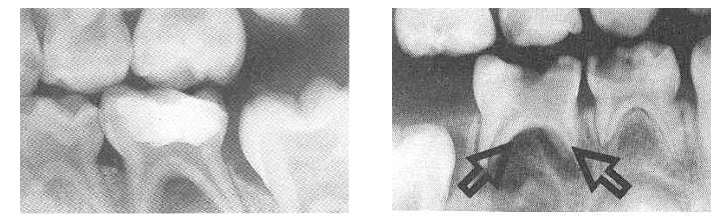

fissures caries model

-once the organic plug fails, bacteria have access to the depths of the fissure

-fissure walls are in close apposition

-unable to detect caries